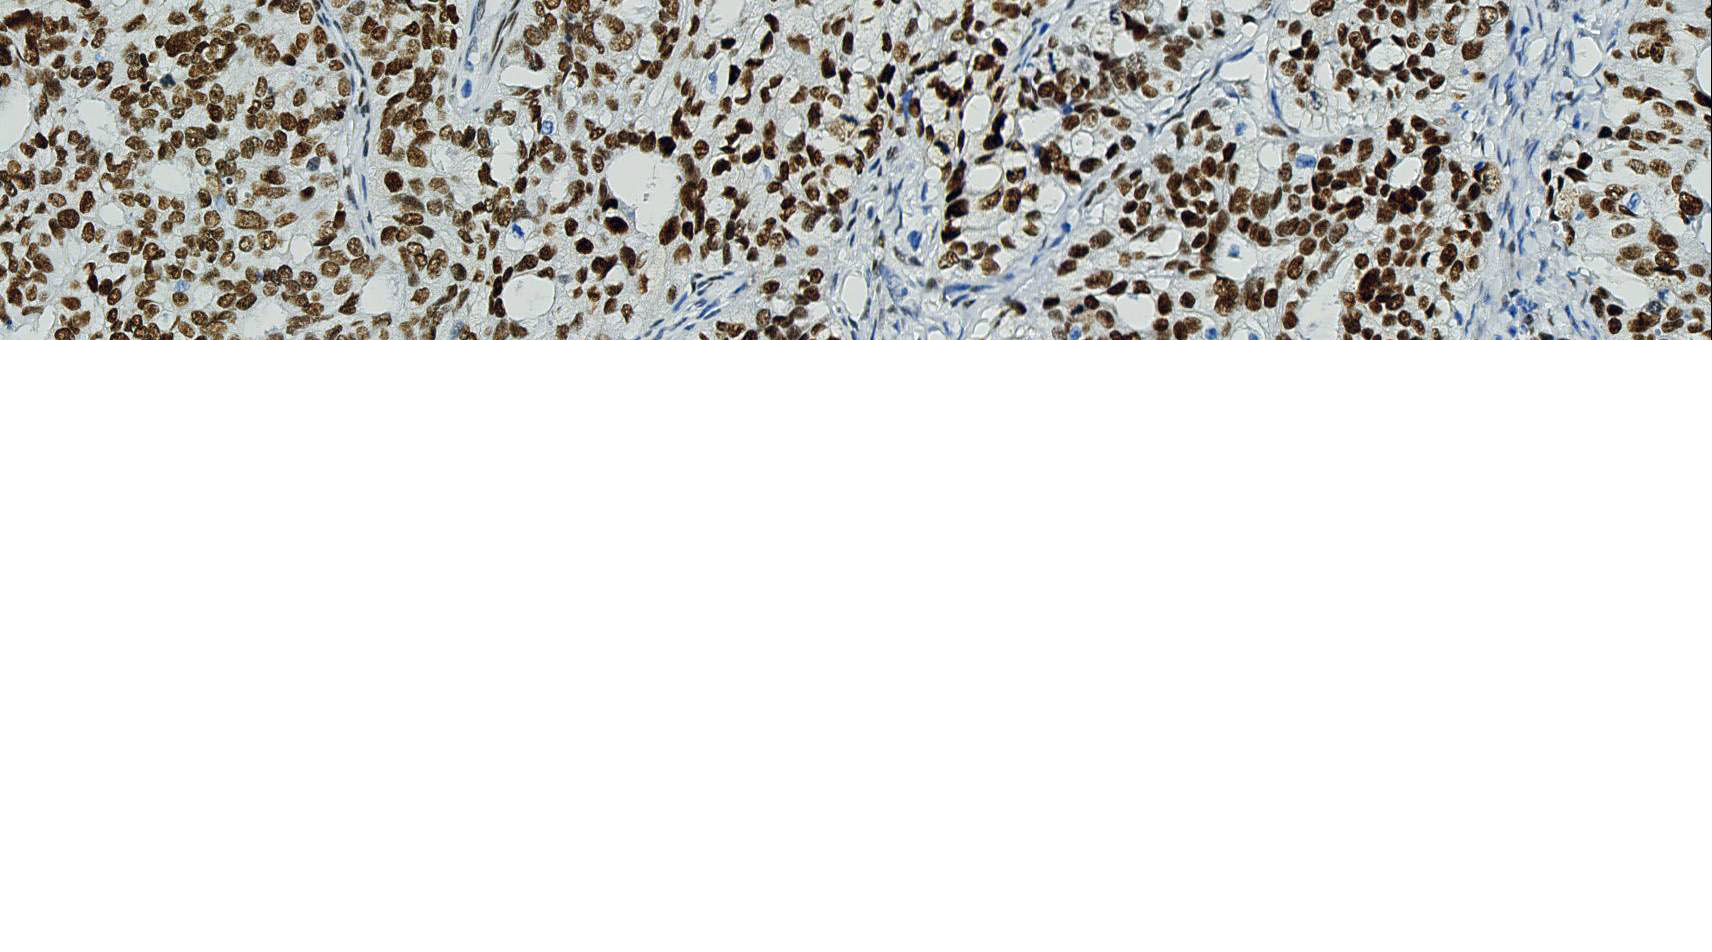

AR

别名: androgen receptor,雄激素受体

信号定位: 胞核